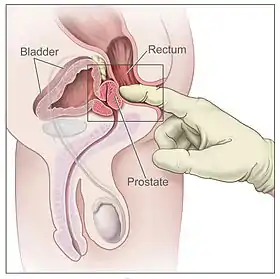

Prostatitis is inflammation of the prostate gland. It can be caused by infection with bacteria, or other noninfective causes. Inflammation of the prostate can cause painful urination or ejaculation, groin pain, difficulty passing urine, or constitutional symptoms such as fever or tiredness.[24] When inflamed, the prostate becomes enlarged and is tender when touched during digital rectal examination. A culprit bacteria may grow in a urine culture.[24]

A digital rectal examination and the measurement of a prostate specific antigen (PSA) level are usually the first investigations done to check for prostate cancer. PSA values are difficult to interpret, because a high value might be present in a person without cancer, and a low value can be present in someone with cancer.[24] The next form of testing is often the taking of a biopsy to assess for tumour activity and invasiveness.[24] Because of the significant risk of overdiagnosis with widespread screening in the general population, prostate cancer screening is controversial.[30] If a tumour is confirmed, medical imaging such as an MRI or bone scan may be done to check for the presence of tumour metastases in other parts of the body.[24]